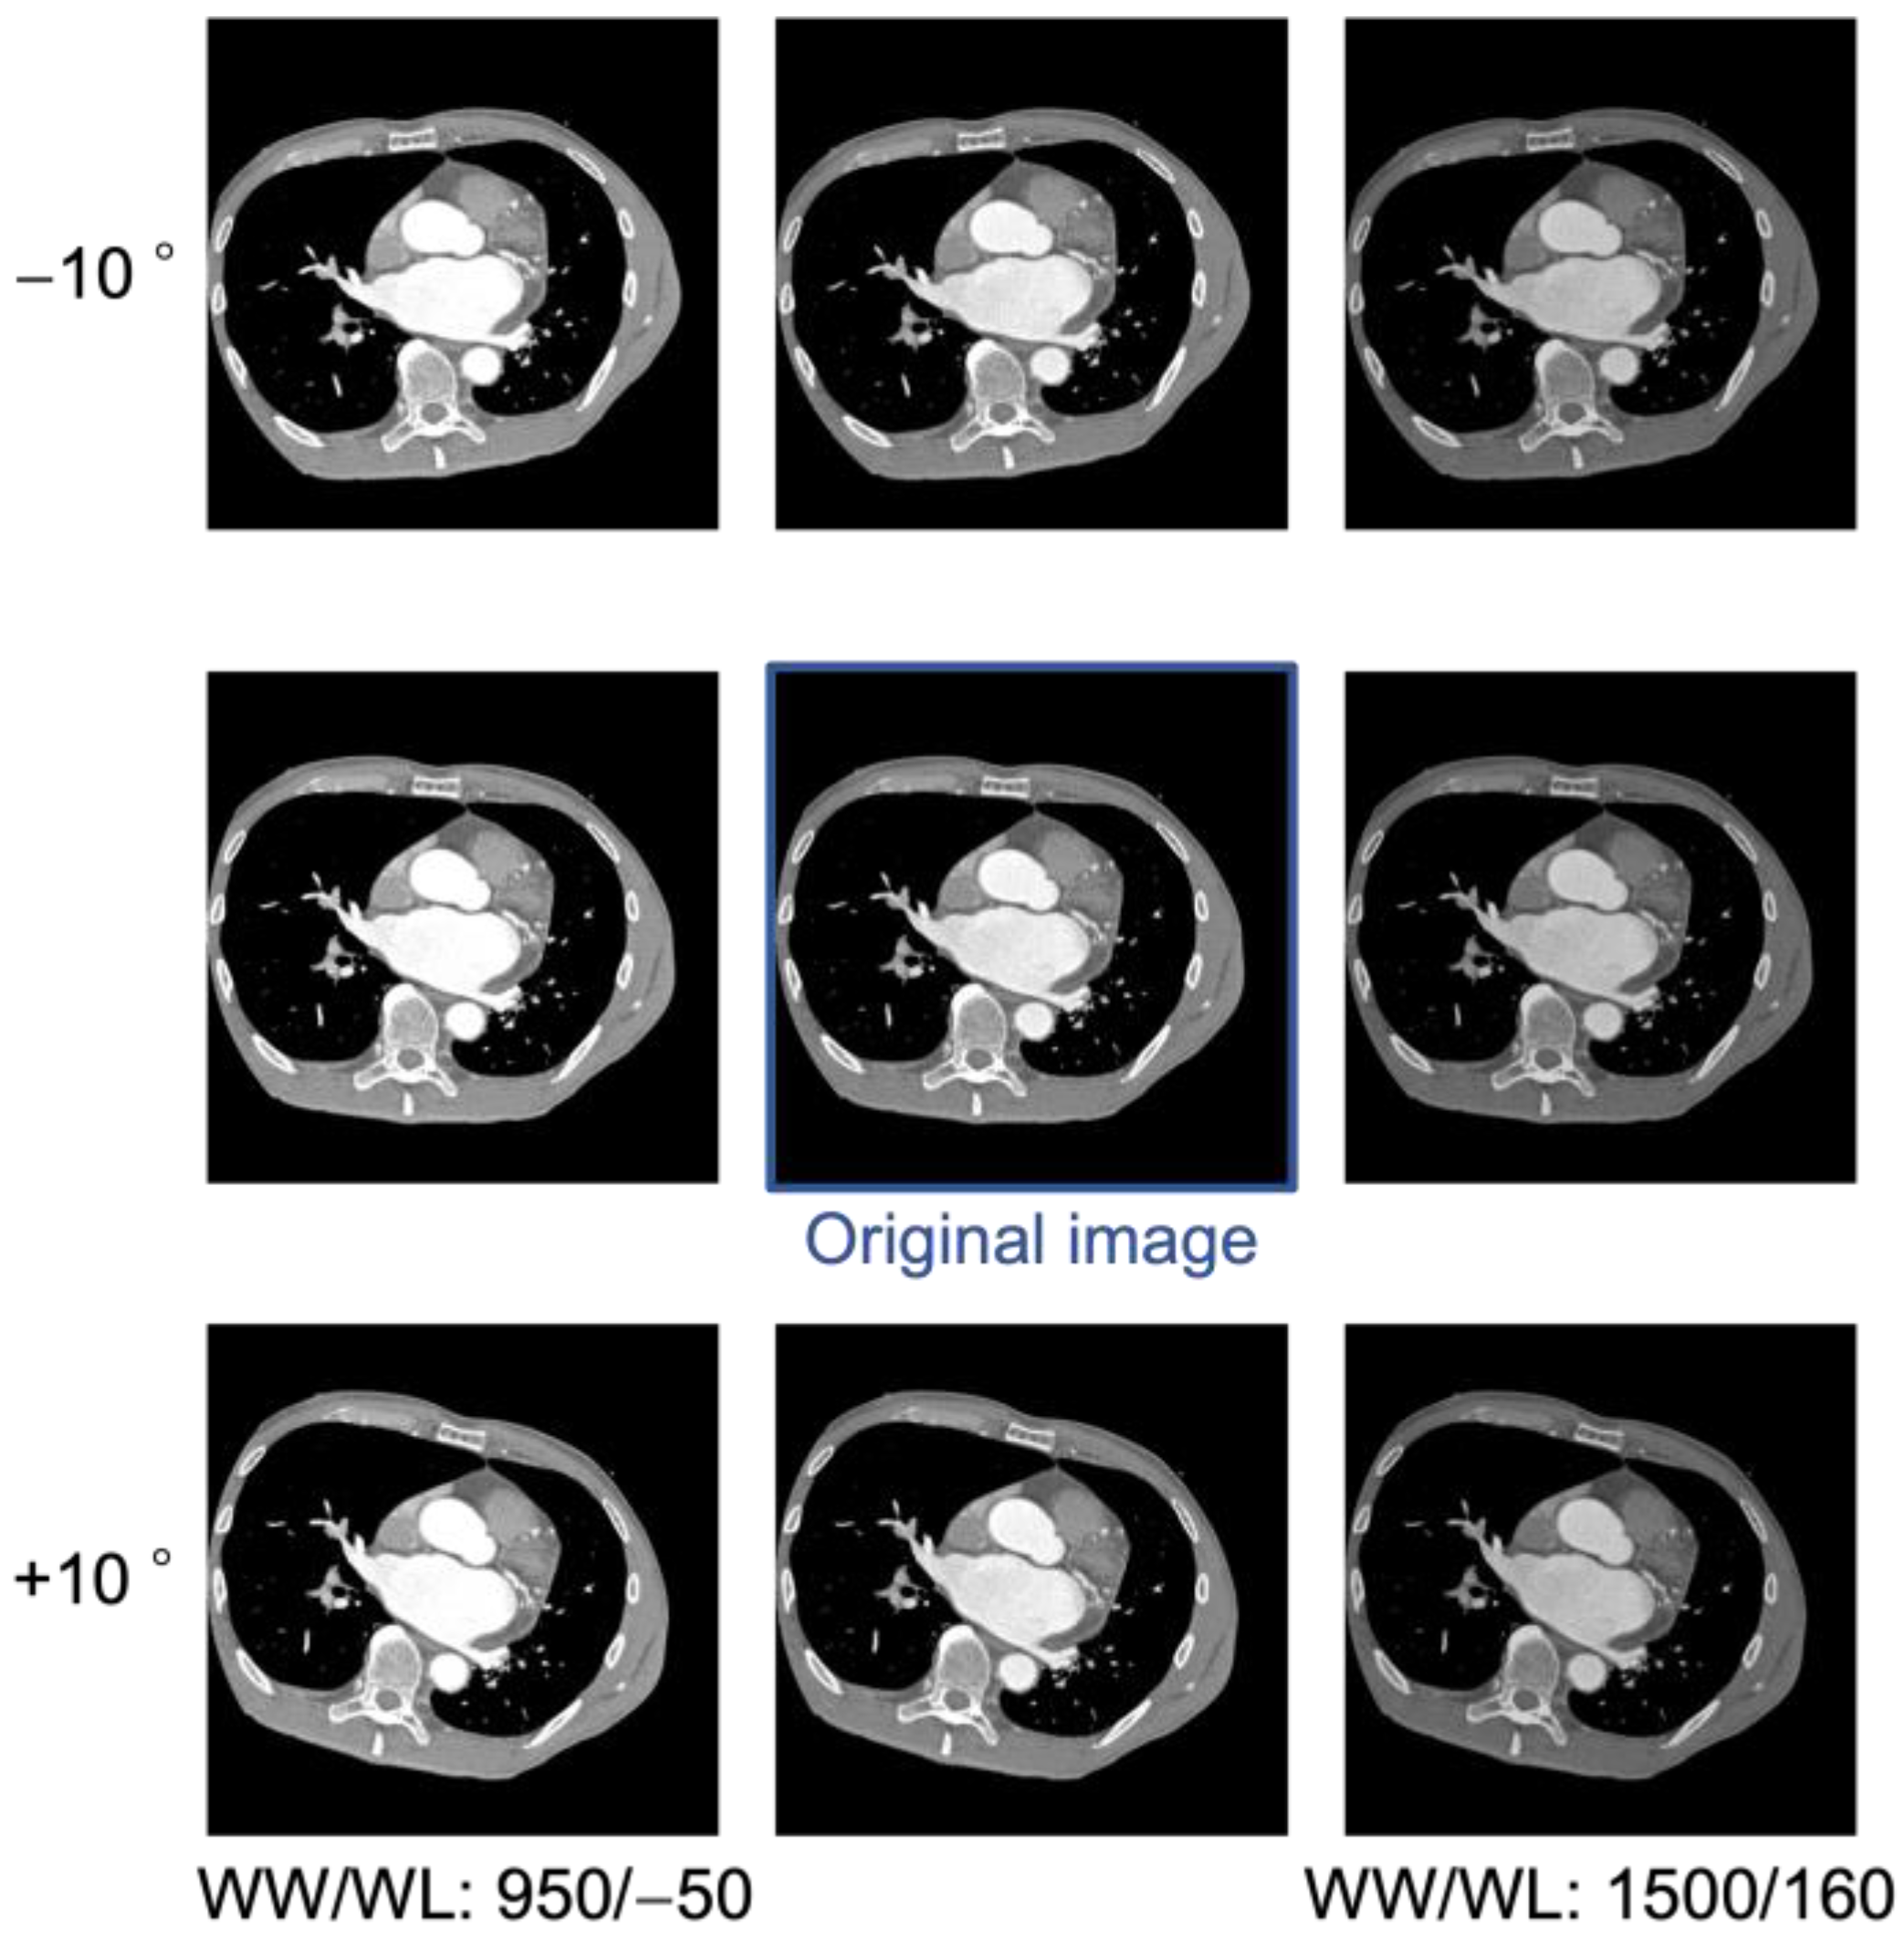

Data augmentation is a method of increasing data by “transforming” image data for training. For example, by rotating, flipping, shifting horizontally, scaling, distorting, adjusting brightness and contrast, and adding noise to an image, various variations can be created. In this study, the number of images increased nine times through data augmentation [19]. CT examinations are usually performed in the supine position; however, in some facilities, the patient is positioned so that the heart, which is located on the left side of the body, is centered in the FOV. In such cases, the curvature of the bed may cause the body to rotate about 10°. To simulate this, the heart was rotated by −10° and +10° for each image, aligning the heart’s tilt to match that observed in the actual CT image. In contrast-enhanced CT examinations, since the density of the contrast agent varies depending on the case, we augmented the pixel values to be robust to changes in pixel values. The CT values of the left atrium were observed across the entire dataset, and the window level (WL) and window width (WW) were adjusted so that the CT values after augmentation fell within the range of real CT images. As a result, in addition to the initial condition of WL = 30, WW = 1000, two variations, including WL = −50, WW = 950 and WL = 160, WW = 1500, were added to increase the number of images threefold. An example of the created image is shown in Figure 2.

Figure 2.

Examples of an original image and images created using data augmentation.